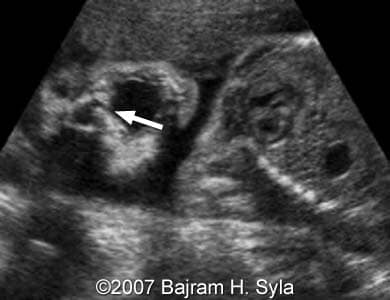

The following images show a case of an unilateral cleft lip detected at 26 weeks of pregnancy.

Images 1 and 2: The image 1 shows a coronal scan of the fetal mouth with the cleft of the upper lip (arrow). The image 2 shows a coronal scan of the opened fetal mouth with the cleft of the upper lip (arrow).